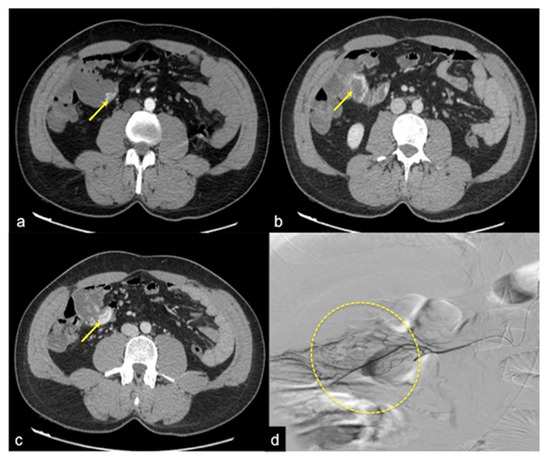

| Aorto-Gastric Fistula (Figure 28) | Copious bleeding. | A connection between the aorta and the gastric lumen. Absence of adipose cleavage planes. |

- Martino, A.; Bennato, R.; Oliva, G.; Pontarelli, A.; Picascia, D.; Romano, L.; Lombardi, G. Primary aortogastric fistula: An extraordinary rare endoscopic finding in the setting of upper gastrointestinal bleeding. Endoscopy 2021, 53, E60–E61. [Google Scholar] [CrossRef]